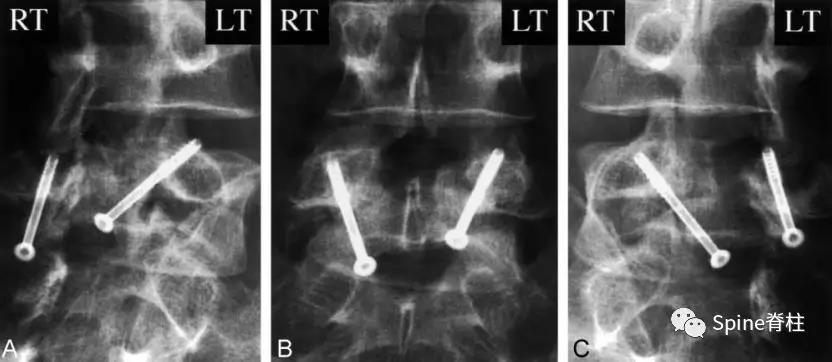

图:起始CT提示L5左侧峡部裂(双箭头),起始CT检查后2个月复查可见出现右侧椎弓根裂(单箭头),4个月复查可见椎弓根裂愈合(单箭头)